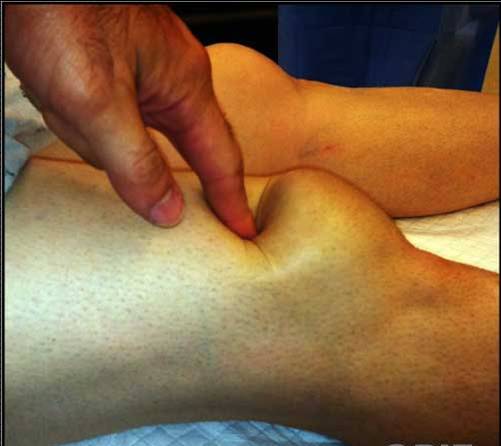

Pga hæmatom og hævelse kan senedefekten være svær at se, men er ofte

tydelig at palpere.